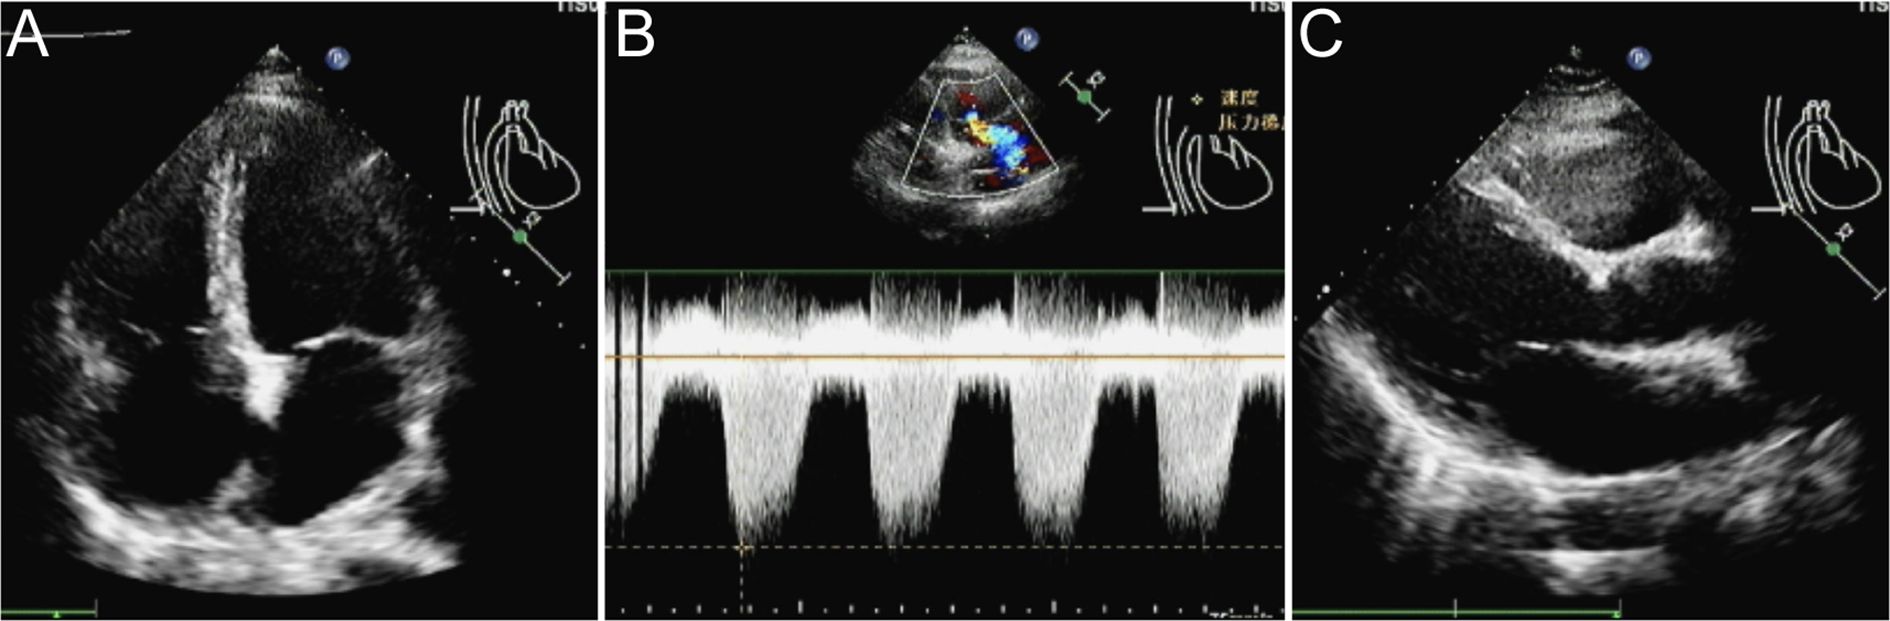

A 35-year-old female was admitted to our emergency department at 3:00 a.m. on February 25, 2024. She complained of palpitations, dizziness, and widespread weakness, along with gingival and vaginal bleeding. The local hospital’s laboratory results indicated WBC 8.1×109/L, hemoglobin 46 g/L, platelets 4×109/L, prothrombin time (PT) 20.7 s (normal range 9-14.5 s), fibrinogen 1.11 g/L (normal range 2-4 g/L), D-dimer 33.39 mg/L (normal range 0-0.5 mg/L), lactate dehydrogenase (LDH) 907.0 U/L (normal range 120-250 U/L), and high-sensitivity cardiac troponin (hs-cTn) 35.4 ng/L (normal range <14 ng/L). The electrocardiogram (ECG) revealed sinus tachycardia, premature ventricular contractions, ST-segment depression, and T-wave anomalies, all of which pointed to anterior wall myocardial ischemia. The patient had a 17-year history of schizophrenia, treated with ziprasidone, lorazepam, and clozapine. On admission, her temperature was 38.4°C, pulse was 130 beats per minute, respiration rate was 21 beats per minute, and blood pressure was 134/74 mmHg. According to the patient’s cardiac ultrasonography, the pulmonary artery systolic pressure (PASP) was 40 mmHg, the left atrium was enlarged, mitral and tricuspid regurgitation, and the left ventricular ejection fraction (EF) was only 44% (normal range 50%-70%) (Figure 1). The proportion of promyelocytes in the peripheral blood smear was 92%. The patient received bone marrow aspiration on the day of admission. The smear showed premyelocytes accounted for 90%. A group of naïve cells that expressed CD33+CD117+CD13+CD64+CD14+CD15+CD56+CD38+ accounted for 91.1% on flow cytometry, and were negative for CD34 and HLA-DR. All the tests indicated APL. We immediately administered ATRA 10mg three times a day plus realgar-indigo naturalis formula (RIF) 1.35g three times a day to reduce the risk of disseminated intravascular coagulation (DIC). The patient’s diagnosis was verified by a follow-up chromosomal and fusion gene (46, XX, t (15,17) (q24;q21) [10], and PML::RARα, respectively).

Figure 1. The cardiac ultrasonography. (A) The left atrium was enlarged, with mitral and tricuspid regurgitation. (B, C) The pulmonary artery systolic pressure was 40 mmHg, and the EF was only 44%.